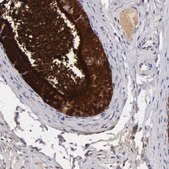

HPA000572

Anti-CLU antibody produced in rabbit

immunohistochemistry: 1:200-1:500